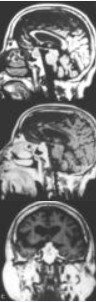

图1垂体腺癌

A.矢位T1WI显示鞍内团块样占位,呈稍低信号。B、C.矢位、轴位T1WI Gd-DTPA增强扫描显示团块明显强化,边界略毛糙,信号欠均

图2垂体腺癌

A、B、C.矢位、冠位T1WI、轴位T2WI显示鞍内团块样占位,呈低等高混杂信号示肿块内出血及坏死,蝶鞍及鞍底骨质破坏蝶鞍扩大。D、E.冠位、矢位T1WI Gd-DTPA增强扫描肿块呈不规则不均匀强化